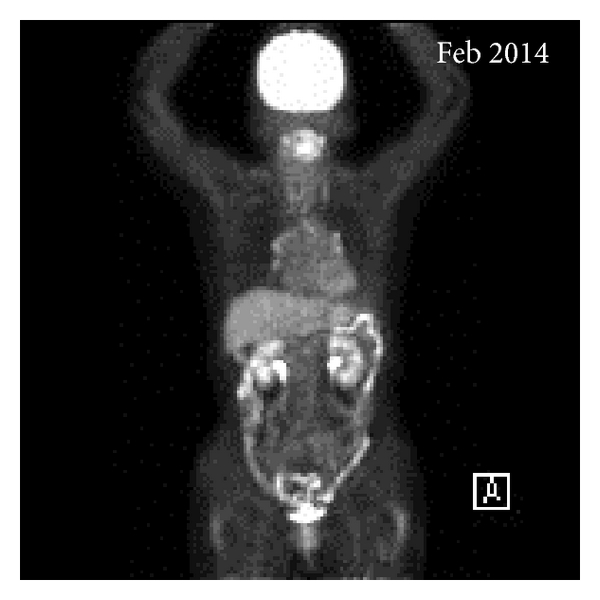

A 75-year-old woman presented with a 6-month history of progressively worsening lumbosacral pain. She was suspected of having myeloma or metastatic bone disease, based on both CT and MRI scans. The CT scan images revealed osteolytic lesions in the ribs and the sacrum without hepatosplenomegaly and lymphadenopathy. The MRI of the lumbosacral spine revealed a heterogeneously enhancing, destructive sacral mass, with focal and diffuse infiltration of the lumbar vertebrae. The laboratory blood values were as follows: hemoglobin of 9.5 g/dL, red blood cells of 2.62 × 1012/L, white blood cells of 3.4 × 109/L, platelets of 150 × 109/L, total protein of 5.23 g/dL (normal range, 6.30–8.20), albumin of 3.39 g/dL (normal range, 4.20–5.40), and elevated β2-microglobulin of 4.5 mg/L (normal range, 0.8–2.4). There was no evidence of a monoclonal protein (M-protein) detected by either serum or urine immunoelectrophoresis and the immunoglobulin concentrations were low, indicating hypogammaglobulinemia: IgG: 435 mg/dL (normal range, 870–1700), IgA: 16 mg/dL (normal range, 110–410), IgM: 11 mg/dL (normal range, 34–250), and IgD: 0.6 mg/dL (normal range, 0–9). In view of the diagnostic difficulties, serum FLC measurements were requested, with the following results: κ FLC concentration of 1.3 mg/L (normal range, 3.3–19.4); λ FLC concentration of 1030.0 mg/L (normal range, 5.7–26.3); and serum κ/λ ratio of 0.001 (normal reference range, 0.26–1.65) (Figure 1). These results indicated the presence of monoclonal λ FLCs, and a diagnosis of myeloma was considered. However, the bone marrow aspirate revealed infiltration with only 2.2% of plasma cells and the chromosomal analysis demonstrated a normal 46,XX karyotype. 18F-FDG PET/CT was performed in order to clarify the diagnosis. It highlighted multiple areas of anomalous concentration of 18F-FDG in the sacrum, iliac bone, pubic, ribs, bilateral femora, and the vertebrae at C2, Th9, Th10, L1, and L2, with a standard uptake value (SUV) between 3.7 and 17.6 (Figures 2(a) and 2(d)). These findings were considered indicative of neoplastic disease and a tissue biopsy was recommended. The sacral tumor open biopsy was performed by an orthopedic surgeon. Hematoxylin and eosin-stained sections of the biopsy specimen revealed marked proliferation of plasma cells and immunohistochemical staining showed that the plasma cells were positive for CD138, IgM, and λ light chain but negative for CD20, CD3, IgG, IgA, IgD, and κ light chain (Figures 3(d)–3(j)). Due to the identification of cytoplasmic IgM, genetic analysis was performed on paraffin-embedded biopsy specimens to rule out WM and IgM MGUS. The MYD88 L265P mutation has been reported to be expressed in both WM and IgM MGUS patients but not myeloma [10]. In the biopsy specimen, MYD88 L265P mutation was not detected by real-time allele-specific polymerase chain reaction (AS-PCR) assays. These results supported the fact that this case was neither WM nor IgM MGUS. Therefore, a diagnosis of MM was confirmed (Durie-Salmon stage IIIA, International Staging System II). The patient was treated initially with ROAD (ranimustine, vincristine, melphalan, and dexamethasone) regimen as the alkylating agent ranimustine (approved for use in Japan) has been reported to have tolerable side effects [11]. Following 2 cycles of ROAD therapy, her general condition and lumbosacral pain improved. Her disease progression was monitored serially using the serum FLC immunoassays, which showed a reduction in the λ FLC concentration from 1030 mg/L at diagnosis (May 2012) to 19.7 mg/L (August 2012). She achieved a very good partial remission (VGPR), defined as a >90% decrease in the dFLC (difference between involved and uninvolved serum FLC levels) [12]. In April 2013, radiographs revealed an undisplaced pathological fracture of the right upper arm bone. A second bone marrow aspirate was also normal with 3.2% infiltration of plasma cells; however the bone marrow clot section identified a microcluster infiltration of plasma cells (Figures 3(a)–3(c)). At this time, the serum λ FLC levels had increased to 422.0 mg/L and the κ/λ ratio was abnormal (0.004) indicating the return of the monoclonal disease. In agreement with these results, a coronal PET/CT scan highlighted multiple foci of metabolic activity and confirmed the clinical relapse (Figures 1, 2(b), and 2(e)). The patient was treated with a regimen of lenalidomide/dexamethasone (LEN/DEX) every 4 weeks. In July 2013, the serum λ FLC concentration normalized (20.1 mg/L) alongside the κ/λ ratio (0.562). In February 2014, 10 months following the initiation of LEN/DEX therapy, the PET/CT images showed complete resolution of the metabolic activity, indicating successful treatment, with the SUV max between 1.8 and 2.3 within the stable lytic bone lesions. At this time, the patient achieved a stringent complete response (sCR) by serum FLC immunoassay, correlating with the PET/CT images (Figures 1, 2(c), and 2(f)).